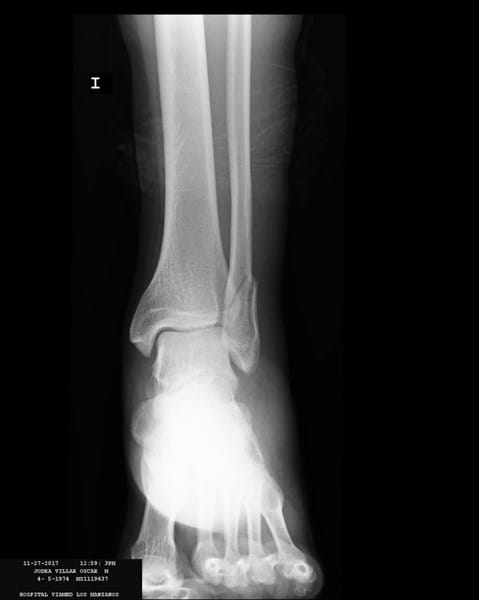

El pasado 25 de noviembre bajando una escalera me retorcí el tobillo izquierdo. Pensaba que había sido un simple esguince y estuve todo el fin de semana con el pie en alto aplicándome hielo y tomando ibuprofeo. El lunes decido ir al medico, me hacen una radiografía y me dicen que tengo: fractura de maléolo peroneo con desplazamiento leve 1,4mm. El traumatólogo me da dos pociones: Una operar o colocar una ortesis fija de tobillo tipo Walker. Después de que me explique que no es necesario operar decidimos seguir adelante con la opción de la ortesis.

Adjunto radiografía